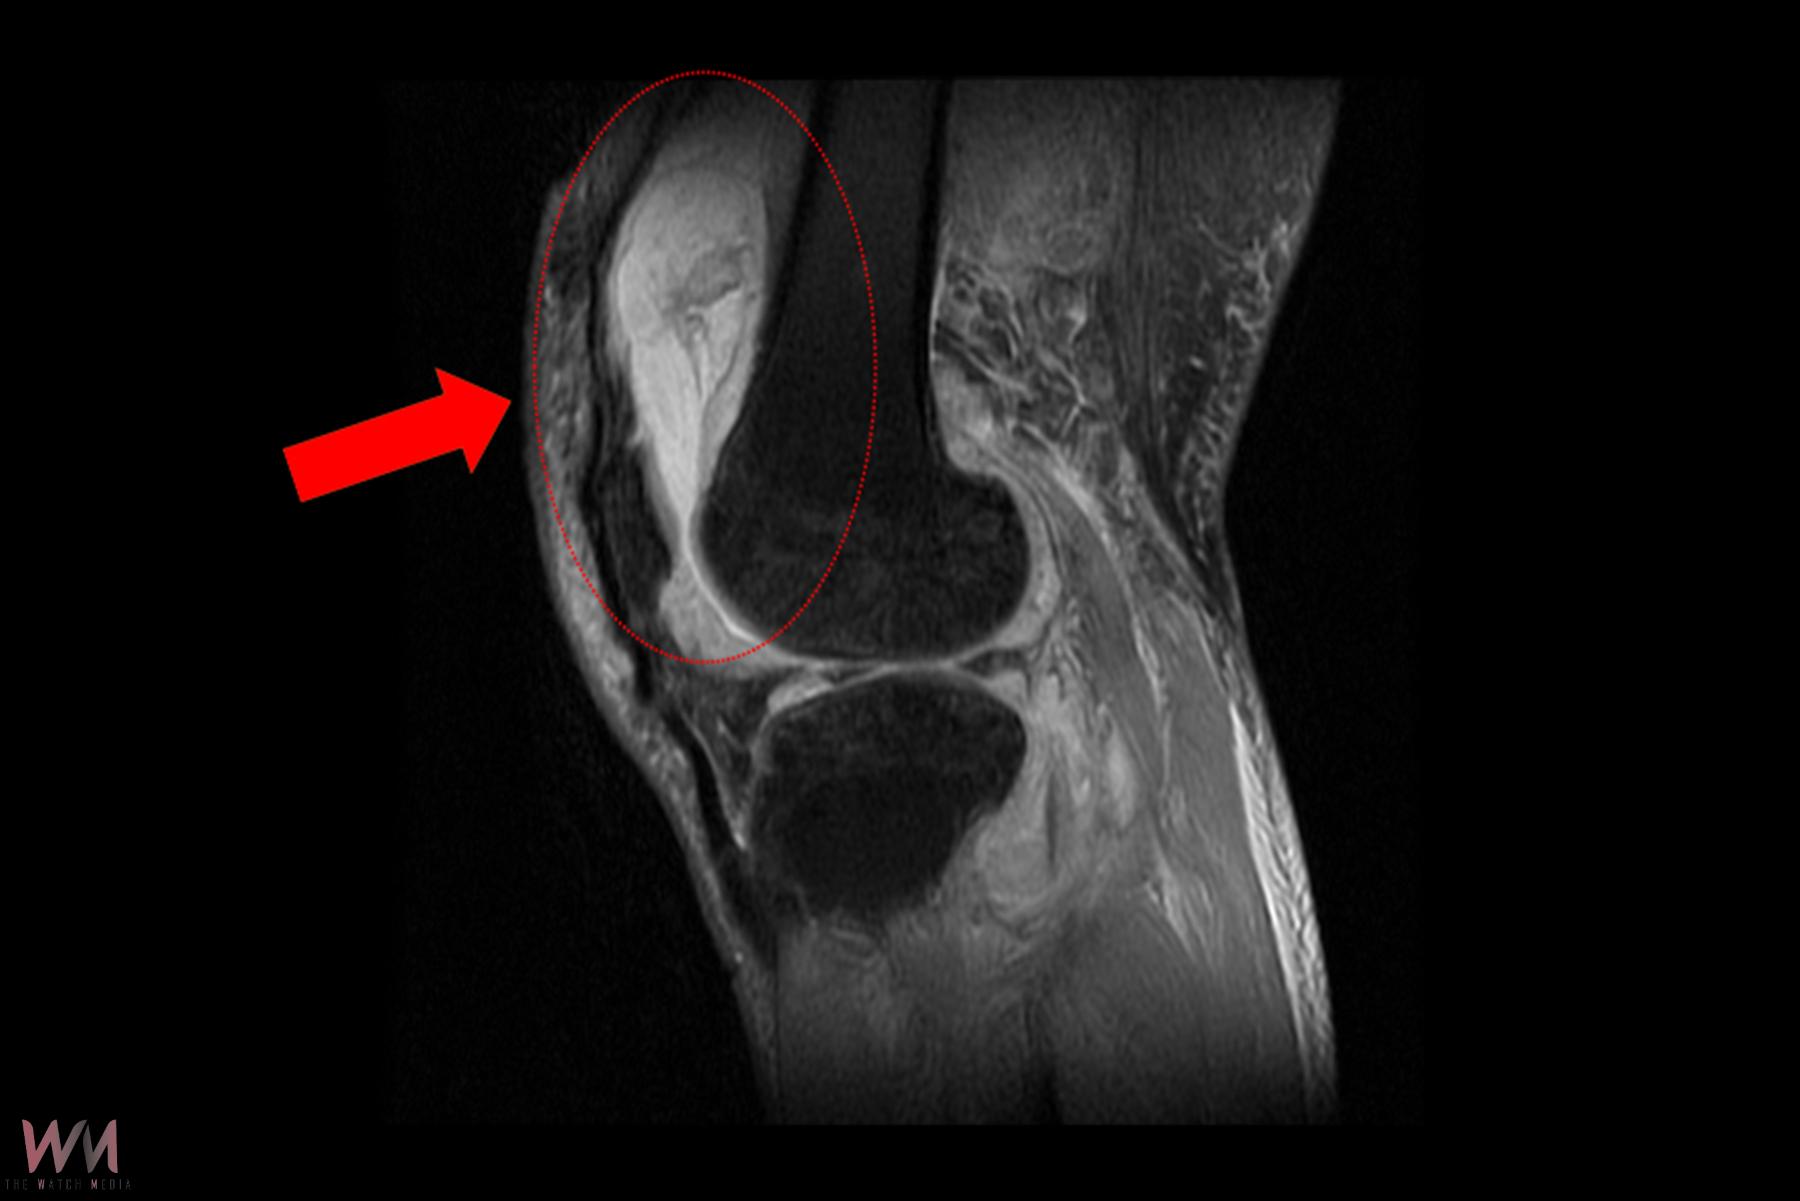

賴先生長期左膝腫痛、幾乎無法行走,就診時表示以為只是退化性關節炎,服用止痛藥、抽關節積水、熱敷復健數月卻越來越嚴重,來院時膝蓋已腫脹無法彎曲。關節中心主任周立展抽取膝關節液化驗後發現,白血球數值雖偏高,但並非典型的細菌感染,懷疑有其他原因。周主任安排病人住院,進一步X光與磁振造影檢查,顯示膝蓋內已有大量積液並化膿,屬於嚴重關節感染。

周立展主任避免病人感染惡化,緊急施行微創關節鏡清創手術,檢體送病理化驗後竟發現結核分枝桿菌,顯示並非單純膝蓋退化。周主任會診感染科與胸腔科醫師共同診斷,在病人痰液培養出結核菌,證實為「肺結核合併肺外感染」。結核菌最初在肺部引起感染,再經由血液或淋巴傳播,最後侵犯膝關節。病人住院期間接受抗結核藥物治療,一周後膝蓋腫脹消退,可正常彎曲行走;出院後仍須持續服藥至少九個月,並定期門診追蹤,確保結核菌完全清除。